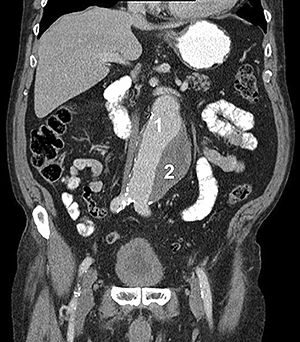

аневризма аорти

Рисунок 2. Комп'ютерна томографія:

1 - зона вільного кровотоку,

2 - тромбована частина аневризми

- доплерографія (дуплексне сканування, УЗДГ): дає змогу виявити порожнину аневризми, стан її стінок, наявність тромбів у її порожнині, інтенсивність кровотоку.

- ангіографія: дає змогу виявити деформацію аорти та її гілок, однак справжні розміри аневризми не завжди видно у зв'язку з можливою наявністю пристінкового тромбозу порожнини аневризми (рис. 2).

- комп'ютерна томографія (КТ) з контрастним посиленням: дає змогу точно виявити межі та форму аневризми й незмінених відділів аорти, обчислити розміри аорти та прилеглих артерій, оцінити ступінь їхньої звивистості. Одна з найбільш інформативних діагностичних методик, абсолютно необхідна для правильного підбору стент-графту.